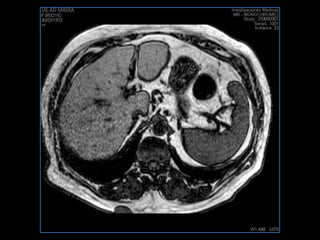

PROTOCOLO hígado graso AXIAL in phase y out phase AX T1 y AX fat sat +SAG T2  CON   GADOLINIO :  COR T1+AX T1(DIN) SAT: NO  FASE: RL THK: 4MM  COIL:  GAP: (FACTOR 1.4)  FOV: 40 CM NEX:2 SINCRONIZACION RESPIRATORIA EN 3 O 4 CICLOS ALE

PROTOCOLO hemocromatosis AXIAL supresión grasa /AX multieco en higado COR T2 AX T1 +SAG T2  CON   GADOLINIO :  COR T1+AX T1 SAT: NO  FASE: RL THK: 4MM  COIL:  GAP: (FACTOR 1.4) 1MM FOV: 40 CM NEX:2 SINCRONIZACION RESPIRATORIA EN 3 O 4 CICLOS ALE

PROTOCOLO pancreas/ riñon AXIAL fat sat /AX in phase out phase AX T1 +SAG T2  COR T2, CON   GADOLINIO :  COR T1+AX T1(DIN) SAT: NO  FASE: RL THK: 4MM  COIL:  GAP: (FACTOR 1.4) 1MM FOV: 40 CM NEX:2 SINCRONIZACION RESPIRATORIA EN 3 O 4 CICLOS ALE